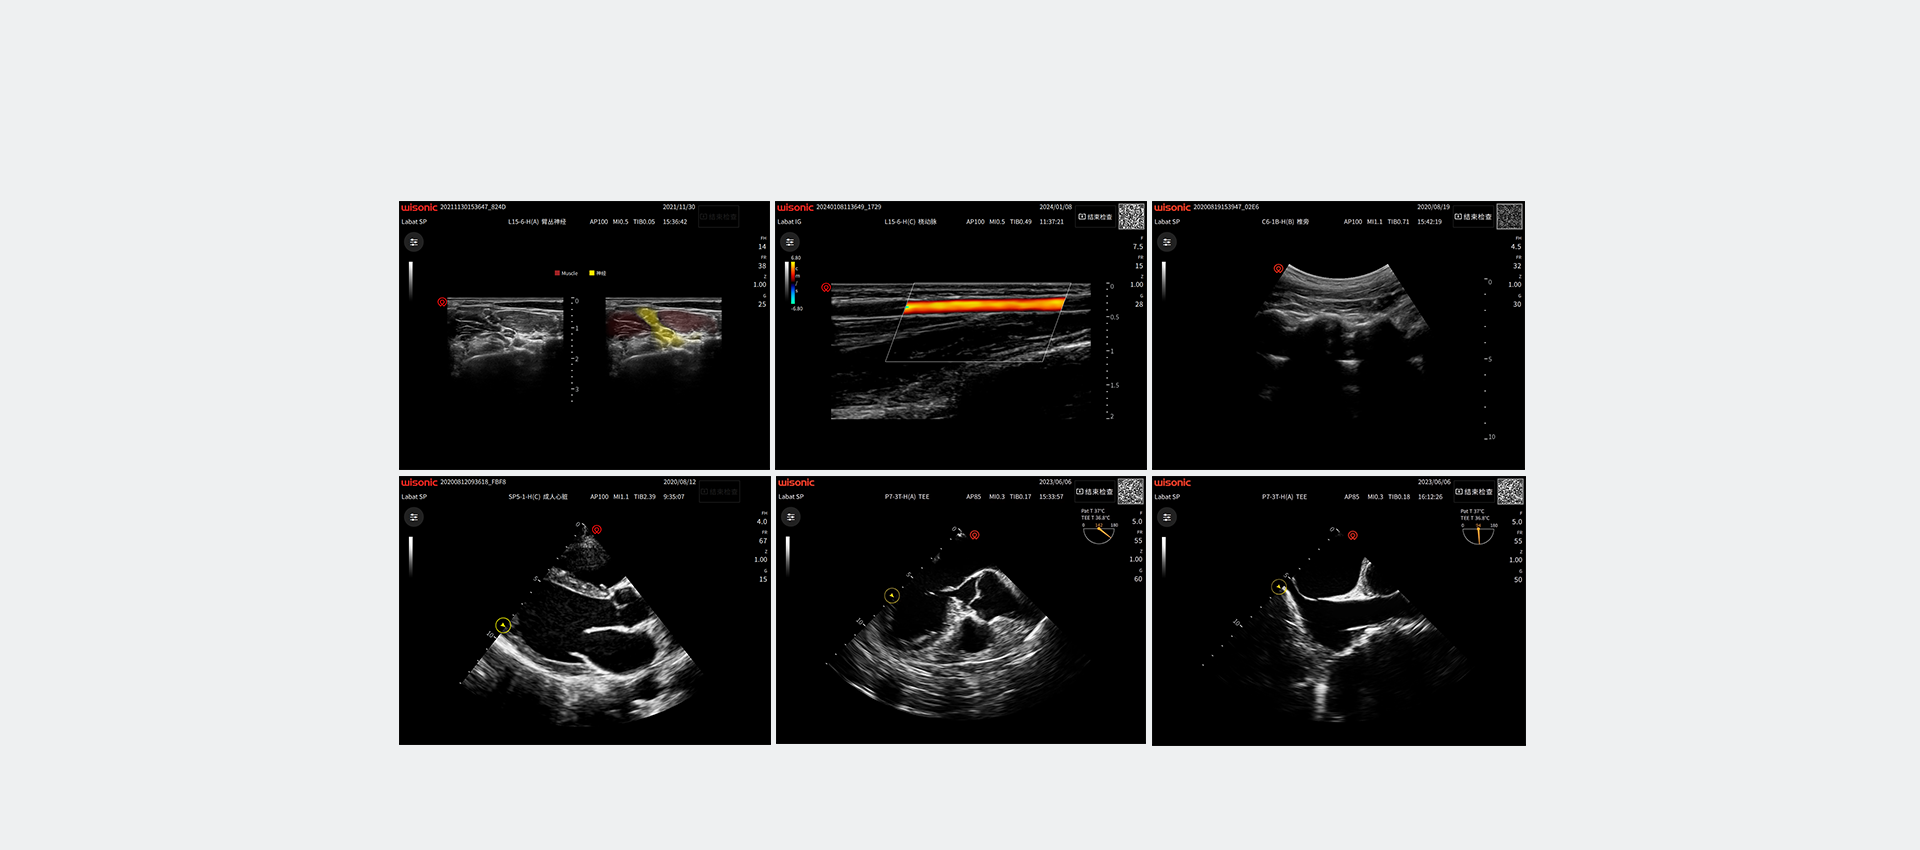

Excellent Clinical Images

Application pictures